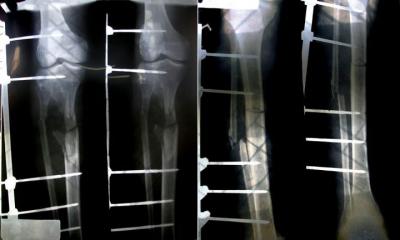

"রাতের বেলা ট্রাকে বালু নিয়া আমিনবাজার থেকে সিঙ্গাইর যাইতেছিলাম। পথে গর্তে পইড়া ট্রাক উল্টাইয়া যায়।আমার দুই পা'ই ভাংছে।আবার কবে হাটতে পারুম আল্লাহই জানেন।"

-মোঃ সোলাইমান,১৮বছর

বালু শ্রমিক

ট্রাক উল্টে আহত

আমিনবাজার,ঢাকা।